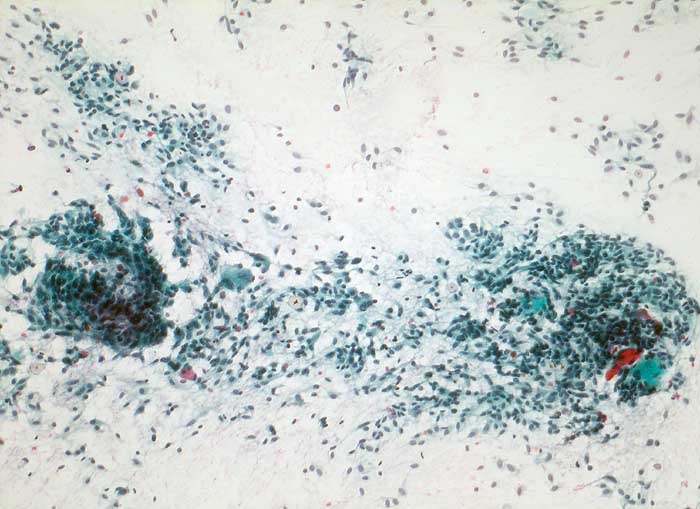

medulläres Schilddrüsenkarzinom

Frischgewebsabstrich: Sehr zellreicher Ausstrich mit grösseren Verbänden spindeliger Zellen und wenig Kolloid.

Patient aus MEN IIA-Familie mit nachgewiesener Mutation des RET-Protoonkogens. Erhöhte Calcitoninwerte nach Pentagastrinstimulation und dringender V.a. medulläres Schilddrüsenkarzinom rechts.

Zytologische Diagnose: medulläres Schilddrüsenkarzinom

Zytologie

100